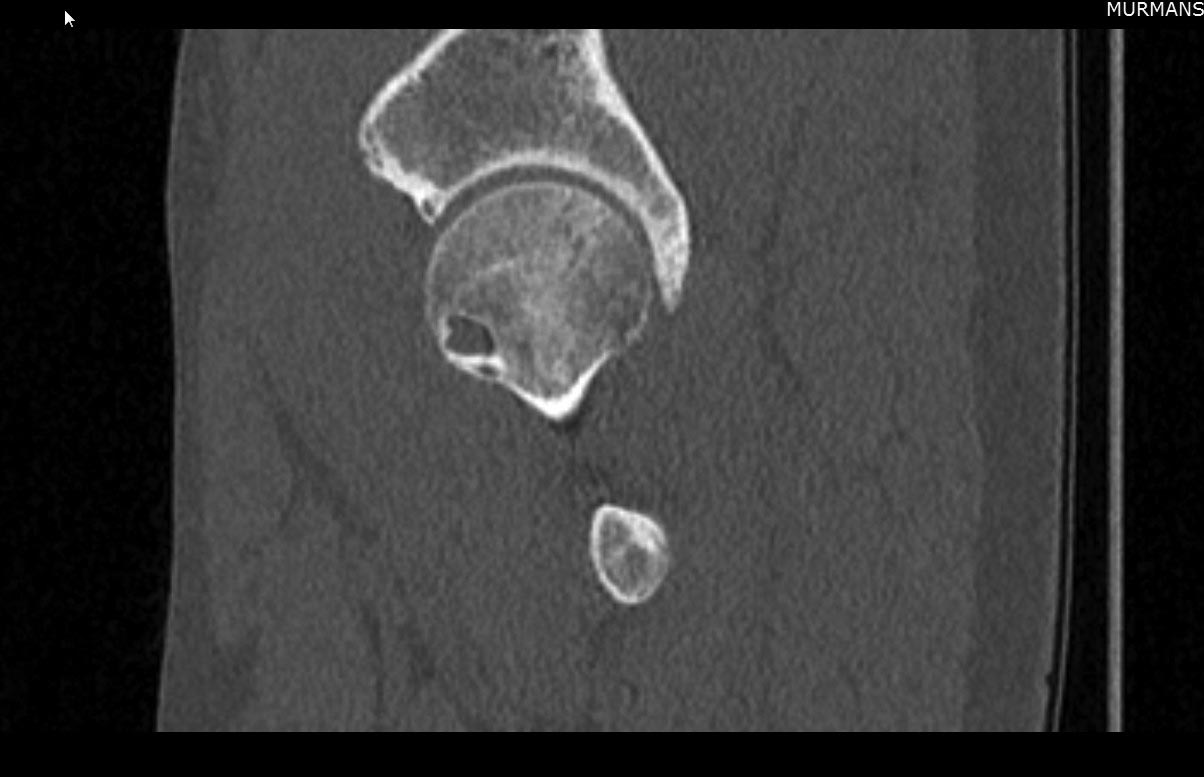

Коллеги, помогите, пожалуйста, с выбором тактики лечения спортсмена. Спортсмен (тайский бокс), тренер, 42 года, пожаловался на боли в ягодичной области, возникающие при подъеме и переносе тяжестей. При тренеровках в полную нагрузку болей нет. Тесты на iliopsoas, наружные ротаторы отрицательны. Есть небольшая болезненность при пальпации в области седалищного бугра. На МСКТ выявлена кистозная перестройка головки правого бедра. Скажите, коллеги, есть ли у пациента альтернативный эндопротезированию вариант. Очень хочется сохранить в нашем городе хорошего тренера для молодого поколения.

Еще КТ

скорее всего причина кист - импинджемент

Если я правильно понял, по КТ - признаки CAM-импиджмента. Но киста располагается по передне-нижней поверхности шейки и головки бедра. Может ли она являться результатом импиджмента?